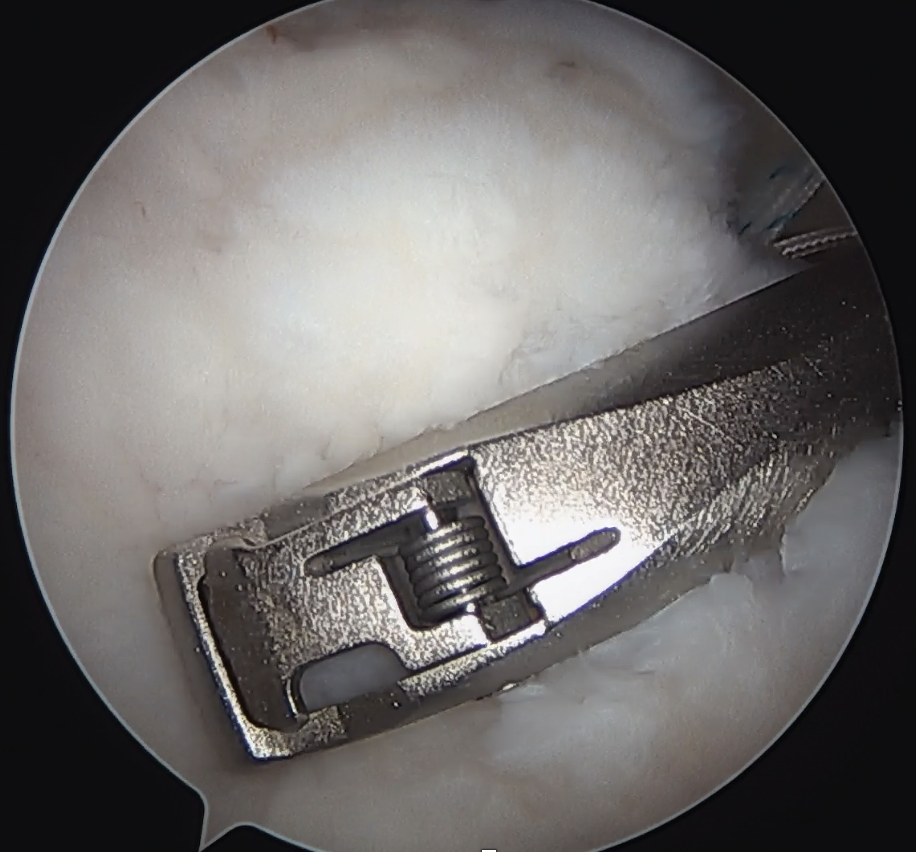

Single row anchor

- insert anchors at lateral edge of footprint

Double row anchors

- medial anchor row at articular margin and tie through medial cuff

- lateral anchor row at lateral footprint used to secure sutures

- increase surface area of cuff repaired to foot print

Medial row anchors

- inserted through additional stab incision for suture management

- just medial to articular cartilage